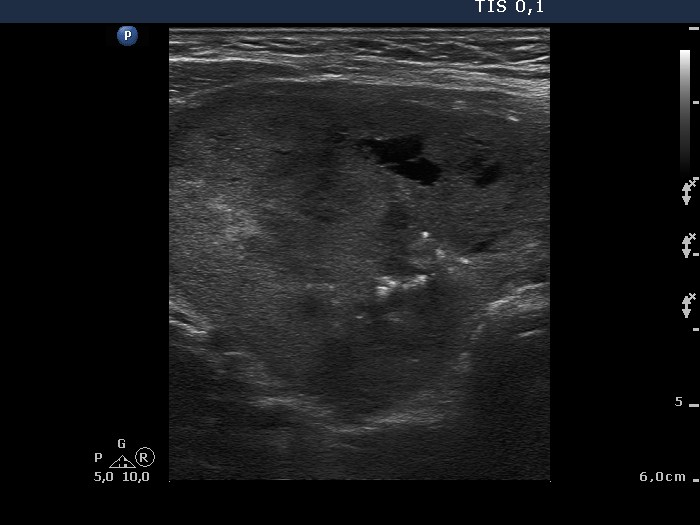

Benign hyperplastic nodule (histological diagnosis) - case 2 |

Hashimoto's thyroiditis without any nodule (histological diagnosis) - case 1520 |

The bright granules lack the dorsal narrowing tail and there are no coexisting similarly bright lines, therefore these granules correspond to punctate echogenic foci.

The coexistence of tiny punctate granules and similarly bright lines is the hallmark of connective tissue. There is a brighter and relatively large granule in the ventral small lesion in the upper image which might be either a punctate echogenic focus or a sign of fibrotic changes.